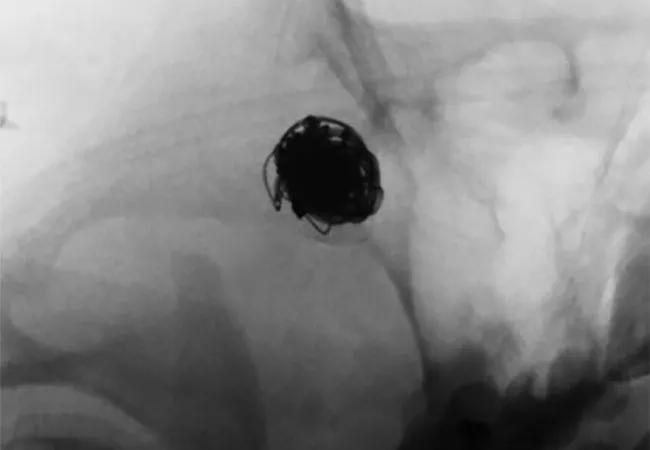

A Pipeline™ embolization device was used for the flow-diverting stent in all cases, placed with a transradial or transfemoral approach. After deployment, diagnostic cerebral digital subtraction angiography was used to assess adequate stasis and to check for kinking, endoleak or parent vessel occlusion.

All aneurysms demonstrated complete occlusion at long-term angiographic follow-up, and no patients developed new complications or neurological deficits. Representative imaging studies from one of the patients are presented in the figure.

Figure. Case illustration of flow-diverting stent use in mycotic aneurysm. (A) A right middle cerebral artery mycotic aneurysm (arrow) was found on a workup of intracerebral hemorrhage in a patient with infective endocarditis. (B) The aneurysm was successfully treated with balloon-assisted coil embolization (arrow) without residual flow into the aneurysm. (C) Magnetic resonance angiography three months later demonstrated residual contrast enhancement at the neck and in the aneurysm lumen suggestive of coil compaction and aneurysmal recurrence (arrow). (D) A flow-diverting stent was successfully placed across the aneurysm neck (arrows). (E) Follow-up angiography at 11 months demonstrated no residual flow into the aneurysm.